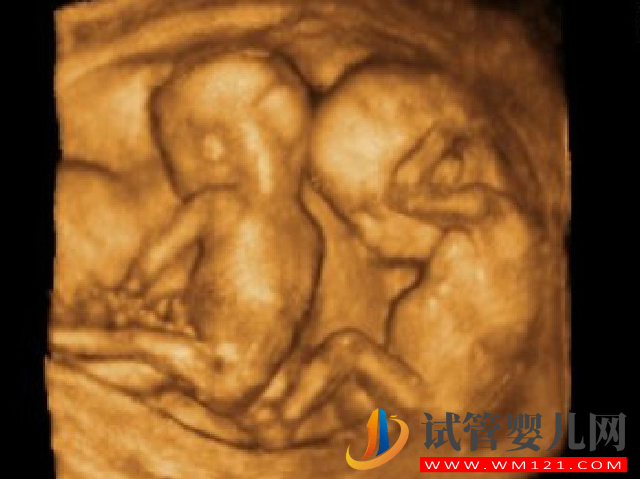

第三代試管樂意說是很多人比較喜歡的一項服務(wù),他不僅可以達到優(yōu)生的情況,還可以滿足更多的生育需求,像是做試管雙胞胎,但是試管雙胞胎不管是對于母親還是對胎兒的風(fēng)險都是很大。

- 1. 第三代試管嬰兒雙胞胎風(fēng)險一般有妊娠期高血壓疾病、早產(chǎn)、貧血、宮縮乏力、羊水過多及胎膜早破、妊娠期肝內(nèi)膽汁淤積癥等情況;

- 3. 胎兒可能會早產(chǎn)或者患上先天性肺病。很多早產(chǎn)兒體重偏低,不少出現(xiàn)3斤重左右的新生兒,甚至還有更低體重的。嬰兒早產(chǎn),如果自身體質(zhì)弱和患有疾病更會影響孩子的一生。而母親考慮早產(chǎn)的可能性需要提前采取預(yù)防措施,以確保嬰兒保持良好狀態(tài)。